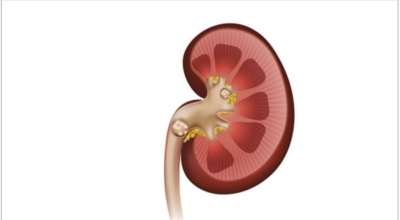

요로결석이란

수분 섭취 감소는 요로결석의 가장 중요한 발병 이유가 되는 것 이라고 합니다. 수분의 섭취가 떨어지면 요석결정이 소변에 머무르는 시간이 길어져 요석형성이 증가하게 되며 요로결석의 발생은 유전적인 소인이 있다는 것이 정설이나 후천적인 생활습관도 관련성을 보입니다.